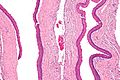

Micrograph of a keratocystic odontogenic tumour. H&E stain.

The definitive diagnosis is by histologic analysis, i.e. excision and examination under the microscope.

Under the microscope, KCOTs vaguely resemble keratinized squamous epithelium;[3] however, they lack rete ridges and often have an artifactual separation from their basement membrane.